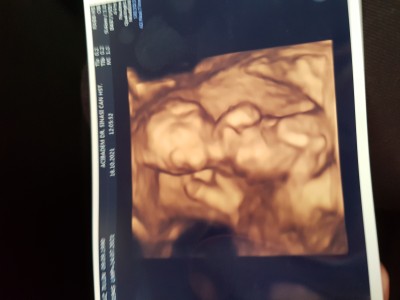

Tahminleri alayım;))

Cinsiyet tahminlerini alayım ;))

13+3

Kız gibi sanki:)

Ağzın bal yesin :)) Benim de gönlümden geçen o inşallah bakalım. Tabi önceliğimiz sağlık. Rabbim hayirlisiyla, sağlıkli, sıhhatli bir sekilde evlatlarımızı kucağımıza almayı nasip etsin inşallah

Kız gibi geldi bana canım gönlünden geçen olsun inşallah